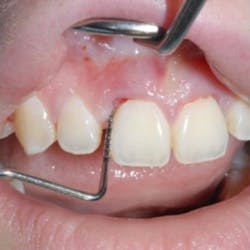

A 22-year-old female presented to a periodontal office with the chief complaint of gum swelling in the maxillary anterior (figure 2). Radiographs taken of the area showed unexpected bone loss in the maxillary central and incisor region (figure 3). The patient admitted to the dentist that she was using a technique known as gap banding that she had found out about online to close the spaces between her front teeth. She stated that she would use these bands at night while she slept, and one morning one of the bands was gone. A few months later, she developed the "swelling in her gums."

The periodontist surgically exposed the area and, after debridement, noticed an orthodontic rubber band encapsulated with fibrous tissue at the alveolar crest of Nos. 8 and 9 (figure 4). The band was then removed (figure 5) and the area was grafted.